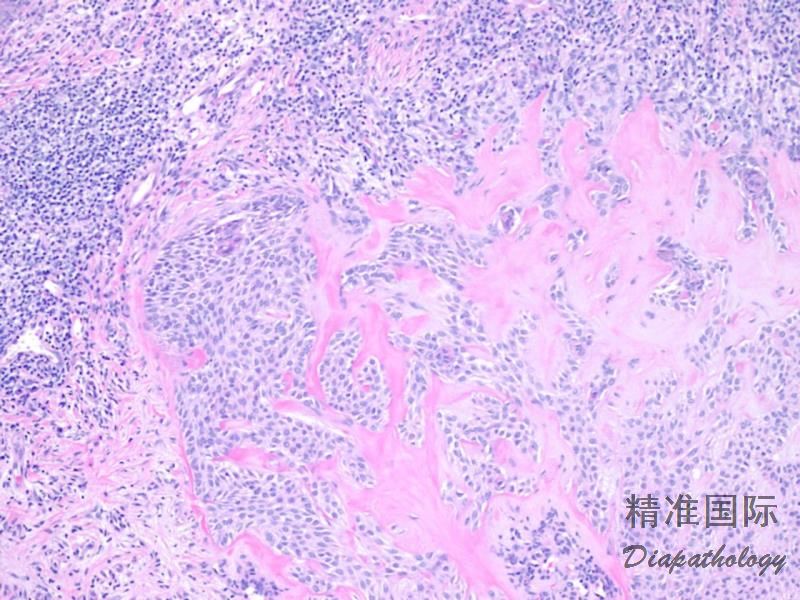

2. 肿瘤以出现细基底样上皮细胞索、角质囊肿和致密的纤维间质三联征为特征;

3. 基底样细胞小。核呈卵圆形,胞浆少,无明显异型性;

5. 间质有大量致密的胶原纤维。

1. 硬化性基底细胞癌: 无角质囊肿,瘤团和间质间有裂隙。